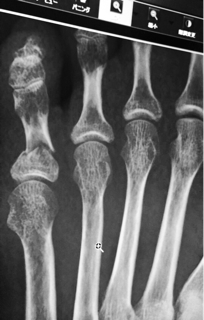

昨夜、フローリングで足を滑らせたわたし。 後方に倒れかかったのを、彼が抱きとめようとするも間に合わず、 ふたりで倒れこんでしまいました。 角で頭をぶつけたみたいだけど、軽い痛みが残っただけ。 それより、彼の踏み込んだ右足が、わたしの左足を捉え、 その時は、軽い痛み程度だったけれど、 今朝になってみたら、内出血が広がっていた。 ドクターの元を受診してみたら、レントゲン写真にがっつり骨折線が。 もしや、まさかの小指を骨折してました。 シーネ固定で包帯保護。 お借りした...